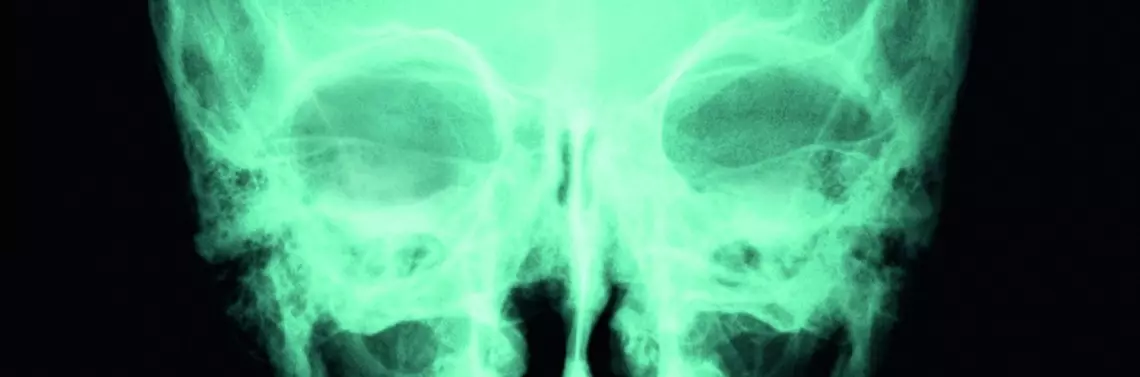

Rehabilitacja w urazach czaszkowo-mózgowych

Urazy czaszkowo-mózgowe to ogólne, aczkolwiek właściwe, kliniczne określenie różnych pod względem przyczyny i skutków urazów okolicy głowy. W krajach europejskich ok. 300 na 100 tys. osób rocznie jest hospitalizowanych z powodu urazu głowy. Urazy tego typu stanowią poważny problem medyczny, socjalny i ekonomiczny, a ich ogólna liczba wciąż wzrasta. Oczywiście większość urazów ma łagodny charakter i generalnie okazuje się niegroźna dla zdrowia poszkodowanego człowieka. Jednak ok. 25 na 100 tys. poszkodowanych osób wymaga hospitalizacji w wyniku umiarkowanego oraz poważnego uszkodzenia głowy, a statystycznie dziewięć z tych osób umiera w wyniku bezpośredniego, pierwotnego uszkodzenia mózgu lub w wyniku wtórnych zmian pourazowych mózgowia.

Urazy czaszkowo-mózgowe są główną przyczyną zgonów osób przed 25. rokiem życia. Około 10–20% osób z poważnym urazem czaszkowo-mózgowym pozostaje trwale niepełnosprawna ruchowo i wymaga stałej, systematycznej, trwającej do końca życia rehabilitacji ruchowej. Szacuje się, że w krajach wysoko rozwiniętych żyje średnio jedna osoba na 1000 po poważniejszym urazie czaszkowo-mózgowym. Warto podkreślić, że wszyscy pacjenci po cięższym uszkodzeniu głowy, a w szczególności przy występujących deficytach neurologicznych, wymagają okresowej i fachowej rehabilitacji ruchowej prowadzonej pod kierunkiem lekarza i fizjoterapeuty posiadającego doświadczenie w pracy z pacjentami z uszkodzeniem ośrodkowego układu nerwowego. Oprócz zabezpieczenia zdrowia i życia pacjenta w fazie ostrej po poważnym urazie głowy decydujące znaczenie dla powrotu do optymalnego zdrowia ma wczesna i właściwie poprowadzona medyczna rehabilitacja funkcjonalna pacjenta.